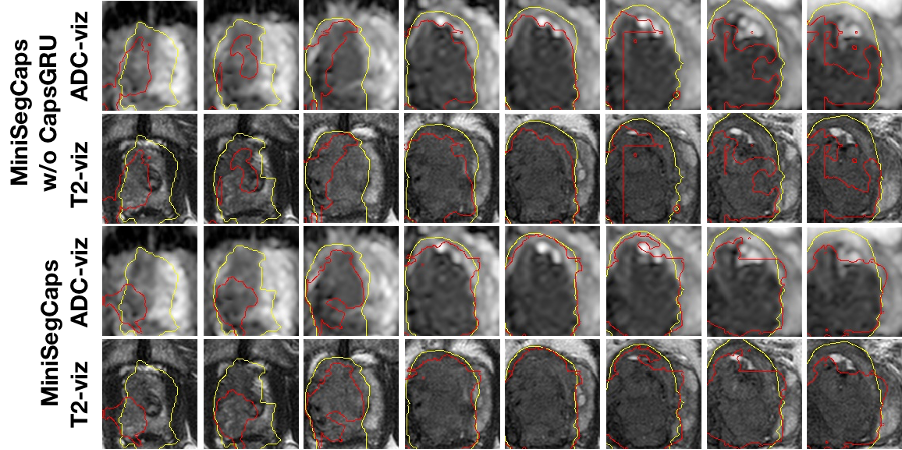

Fig.3 illustrates a visual comparison of the cropped T2, cropped ADC, cropped zonal mask, lesion ground truth, and predicted lesion mask by MiniSegCaps on T2 and ADC images. Our model successfully produced satisfactory segmentation of prostate cancer and revealed the spatial relationship between the zonal mask, lesion on T2, and ADC, which might help lesion location and classification. We also obtained consistent segmentations across adjacent slices within one volume, as shown in Fig.4. Our MiniSegCaps obtained better results than MiniSegCaps w/o CapsGRU, which indicates that CapsGRU captured the spatial information across adjacent slices as expected, boosting the prostate cancer segmentation performance. Moreover, our model achieved acceptable performance on BPH segmentation as shown in Fig.6.

Fig. 4. Visualization of lesion segmentation results on eight slices from one case. The yellow contour is ground truth, and the red contours are predictions from the MiniSegCaps without or with CapsGRU. MiniSegCaps with CapsGRU can better delineate the prostate cancer contours across different slices in one case compared to that without CapsGRU.